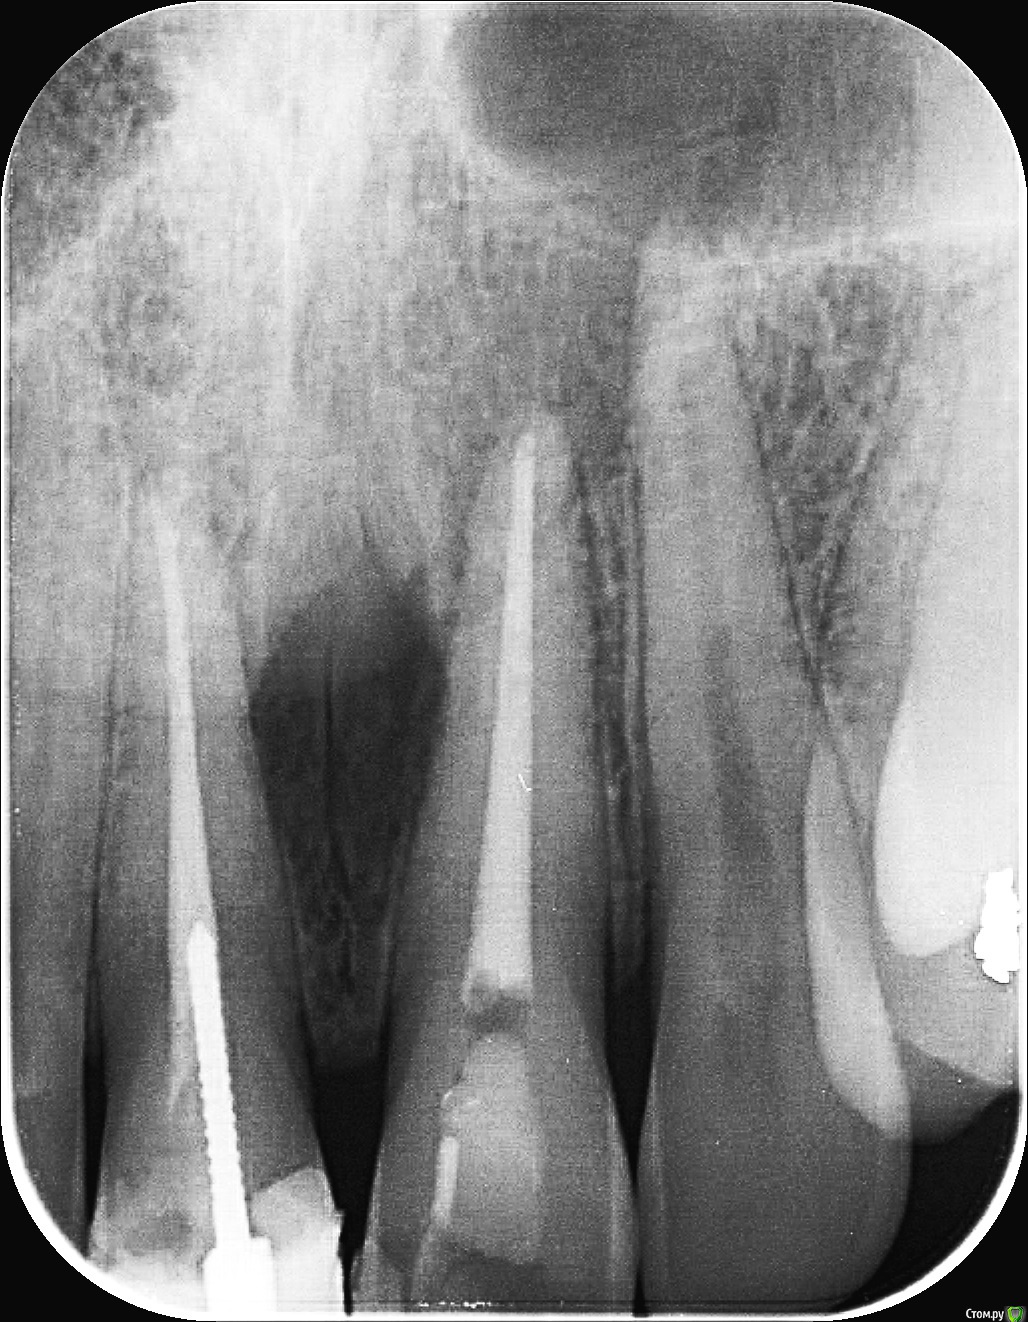

vlazub Опубликовано 5 февраля, 2019 Автор Поделиться Опубликовано 5 февраля, 2019 сделал КТ - в 3D-режиме видно что нет передней стенки кости над верхними резцами[/url][/url][/url][/url][/url] Ссылка на комментарий

vlazub Опубликовано 5 февраля, 2019 Автор Поделиться Опубликовано 5 февраля, 2019 11 зуб попадает в кисту[/url] Ссылка на комментарий

vlazub Опубликовано 5 февраля, 2019 Автор Поделиться Опубликовано 5 февраля, 2019 21 зуб[/url] Ссылка на комментарий

vlazub Опубликовано 5 февраля, 2019 Автор Поделиться Опубликовано 5 февраля, 2019 киста м-ду 11 и 21[/url] Ссылка на комментарий

vlazub Опубликовано 5 февраля, 2019 Автор Поделиться Опубликовано 5 февраля, 2019 корень 22 здорового зуба в кисте[/url] Ссылка на комментарий

Дмитрий Л. Опубликовано 5 февраля, 2019 Поделиться Опубликовано 5 февраля, 2019 Правильны ли мои догадки? И какие дальнейшие действия в моем случае?В вашем случае нужно поторопиться найти хороших врачей. Предположительно перелечить центральные резцы и возможно пролечить боковой левый. Может быть потребуется хирургическое вмешательство, но не в плане удаления зубов, а в плане "чистки кисты". На форуме есть хорошие специалисты. 2 Ссылка на комментарий

___49___ Опубликовано 6 февраля, 2019 Поделиться Опубликовано 6 февраля, 2019 +1 за хирургию с предварительной подготовкой 2ки . У центральных каналы пролечены хорошо , для хирургии не трогал бы . 1 Ссылка на комментарий